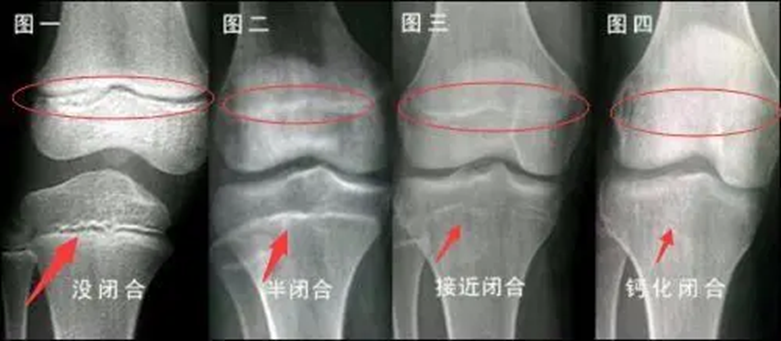

骨骺线闭合过程示意图 来源 | 百度百科

人全身的发育状况可以从骨骼发育中窥见一斑,骨骼的发育又与骨骺的形态有着密切的联系。骨骺有四个生长阶段:生发期、增殖期、塑形期以及闭合期,骨骺的发育受到很多因素的影响,但是生长阶段不会因为骨的发育而有所提前。所以可以从骨骺的生长时期情况判断骨是否还在生长。

人体骨骼在发育的过程中,骨头两端的软骨中出现的骨化点称为骨骺。在人体骨骼还未成熟时,一些骨骼还呈现软骨的状态。当身体发育完成,这一部分软骨就会完全骨化,变成一条紧密的缝。一般在16至20岁之间人体会完全长成,骨骺线闭合,身高固定下来,当然也会因为个体的差异而有所不同。